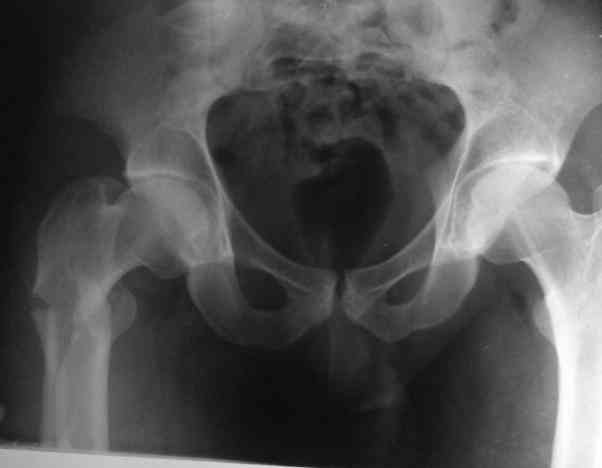

Male, 75 yrs old.

Right hip fracture as an interthrocanteric with extension to diaphysis Tronzo V.

Option for treatment:

1. DHS

2. 90 - 95 g AO Plate (Condylar Plate)_

3. Reconstruction Hip Nail

4. Intertrochanteric Nail System

5. Externa hip fixator

6. None of the above.